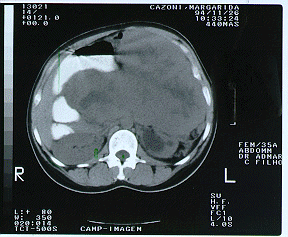

Tomografia computadorizada de abdome(imagem 1 e imagem 2)